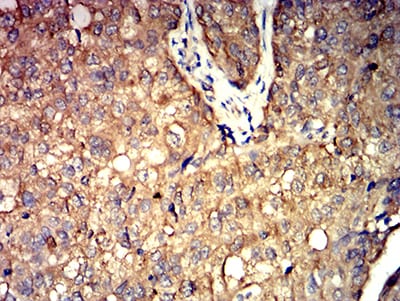

Immunohistochemical analysis of paraffin-embedded human bladder cancer tissues using ALDOA mouse mAb with DAB staining.